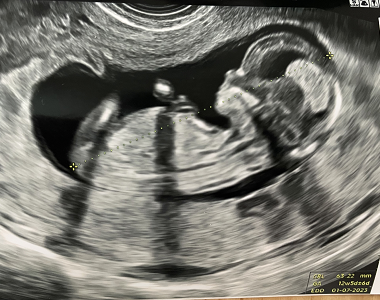

Screening v 1.trimestru

Ahoj bolky :)Tak jsme teď v pondělí byli na 1. velkém UTZ bylo to něco úžasnýho a nezapomenutelnýho!!! Viděli jsme toho našeho andílka snad ze všech stran, pan doktor nám vše vysvětloval, slyšeli jsme...